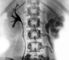

Туберкулезный папиллит может проявляться болями в поясничной области, почечной коликой, гематурией. Характерны «асептическая» лейкоцитурия, эритроцитурия и протеинурия. У больных, которые в прошлом лечились противотуберкулезными средствами по поводу туберкулеза других локализаций, микобактерии туберкулеза при бактериологическом и биологическом исследовании мочи могут не обнаруживаться. При рентгеноконтрастном исследовании верхних мочевых путей (экскреторной урографии или ретроградной пиелографии) выявляют небольшие дополнительные тени в области свода одной или нескольких почечных чашек, в более поздних стадиях — деструктивный процесс в почечных чашках (рис. 7), сопровождающийся стенозом или рубцеванием их шеек. В отличие от папиллитов нетуберкулезной этиологии, главной особенностью которых является постоянство урографической картины на протяжении длительного периода наблюдения, для туберкулезного папиллита характерна положительная или отрицательная урографическая динамика.

При кавернозном туберкулезе почек субъективные симптомы те же, что и при туберкулезном папиллите. Выявляют пиурию, микобактерии туберкулеза в моче (при бактериоскопии, культуральном и биологическом исследовании). При экскреторной урографии или ретроградной пиелографии (рис. 8) обнаруживают рентгенологические признаки разрушения почечного сосочка либо каверну в мозговом веществе почки, не сообщающуюся или сообщающуюся свищевым ходом с чашечно-лоханочной системой. Обтурация или облитерация просвета шеек почечных чашек или мочеточника сопровождаются болями в поясничной области, иногда почечной коликой, рентгенологически характеризуются прогрессированием ретенционных изменений вплоть до гидронефротической трансформации почки с резким подавлением ее функции.

По клиническим проявлениям фиброзно-кавернозный туберкулез почек сходен с кавернозным. При рубцевании шеек отдельных почечных чашек на экскреторных урограммах и ангиограммах выявляют «выключение» соответствующих сегментов почки (рис. 9). Рубцевание лоханочно-мочеточникового сегмента или тазовой части мочеточника приводит к подавлению секреторной и экскреторной функции почки и к тотальному ее «выключению». Участки сегментарного или тотального «выключения» почки могут подвергаться обызвествлению или рубцовому сморщиванию, что может быть причиной артериальной гипертензии. У больных туберкулезом обеих или единственной почки преобладает симптоматика хронической почечной недостаточности.